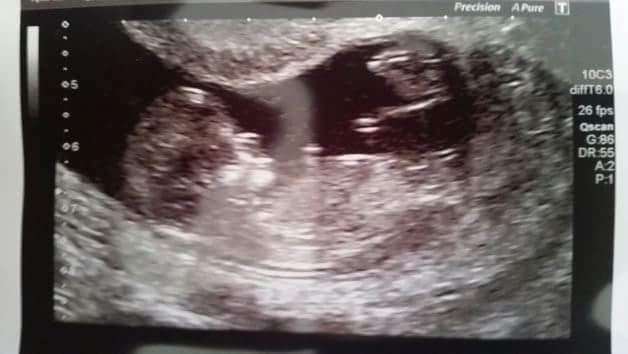

Our first ever look at our little Fox cub – when we were told to expect a Christmas Day arrival!

20 week scan – our baby girl chews some toes!

At 20 weeks, our resolved to remain neutral and enjoy a surprise at birth was destroyed as soon as the sonographer carrying out my scan informed us they could tell us what baby was. “Well, if you know”, Kev told them, “I have to know!” And so we learnt our firstborn was a beautiful daughter and my bump was immediately christened Imogen. She was never going to be anyone else and her name belonged to her long before birth.